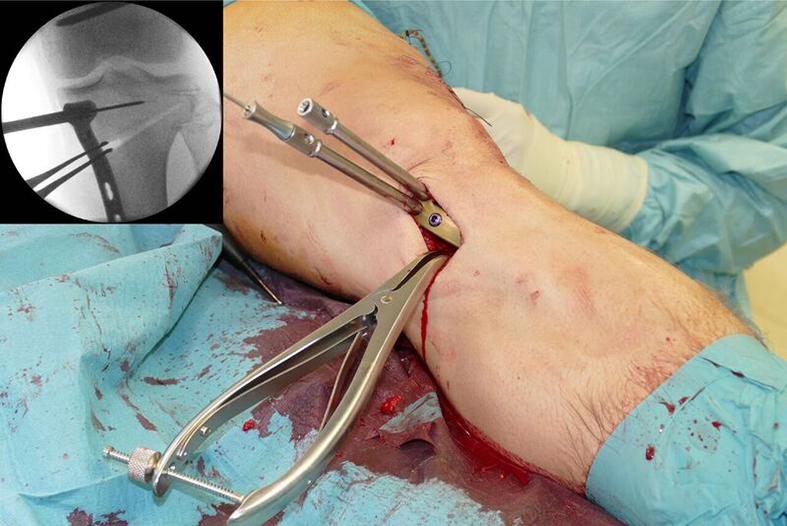

Surgery was initiated with an arthroscopy. No cartilage lesion was observed and removal of the lateral staples followed. The osteotomy started at the femur as a lateral closed wedge biplanar DFO. The new radiolucent hook from the TomoFix Anatomical system was tested during this aspect of the procedure. The hook is ideal in the adoption of a minimally invasive approach for use in patients with normal soft tissue (Fig 9).

Following completion of the DFO and fixation with the TomoFix MDF Anatomical (Fig 10) the new aiming arm and K-wire guide system was used for the open wedge HTO.

After performing a minimally invasive approach at the medial proximal tibia, the first step of the new K-wire guiding system is definition of the hinge point with a K-wire from the lateral aspect (Fig 11). The guiding arm for the osteotomy was then inserted with the radiolucent hook in situ (Fig 12). The guiding arm should be adjusted under intensifier control and finally fixed with a K-wire. At this stage two K-wires for the osteotomy can be inserted and the guiding arm can be removed. The saw guide is then mounted and guides the sawblade safely (Fig 13 and 14).